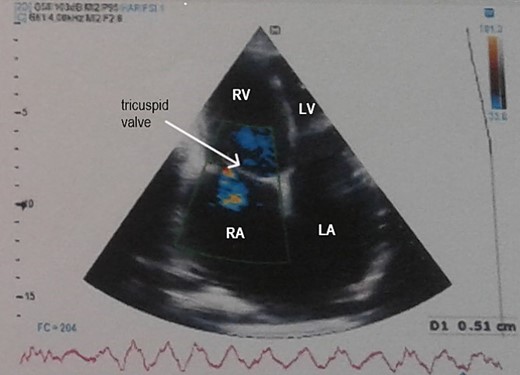

Electrocardiogram (Fig. 1) showed an atrial fibrillation at 120 c/mn with normal axis and a T wave inversion in anterior. Chest radiography (Fig. 2) revealed pericardial calcifications and a mild cardiomegaly. Transthoracic echocardiography (Figs 3–5) showed a pericardial thickening, an important distension of left atrium (LA diameter = 66 mm, LA surface = 33 cm2) and the inferior vena cava (23.7 mm), a calcified mitral leaflets as well as the subvalvular apparatus, restriction of the posterior mitral leaflet with moderate mitral regurgitation (Pisa: 6 mm and ERO: 35 cm2), dilated right heart cavities with moderate tricuspid regurgitation and severe pulmonary hypertension (62 mmHg), preserved left ventricular systolic function (EF LV: 63%) with paradoxical septum. The patient was on lasilix 40 mg one tablet per day, aldactone 50 mg one tablet per day and digoxin 0.25 mg one tablet per day.

Transthoracic echocardiography showed pericardial thickening, moderate tricuspid regurgitation and biatrial dilation. RA: right atrium, RV: right ventricle, LA: left atrium, LV: left ventricle.